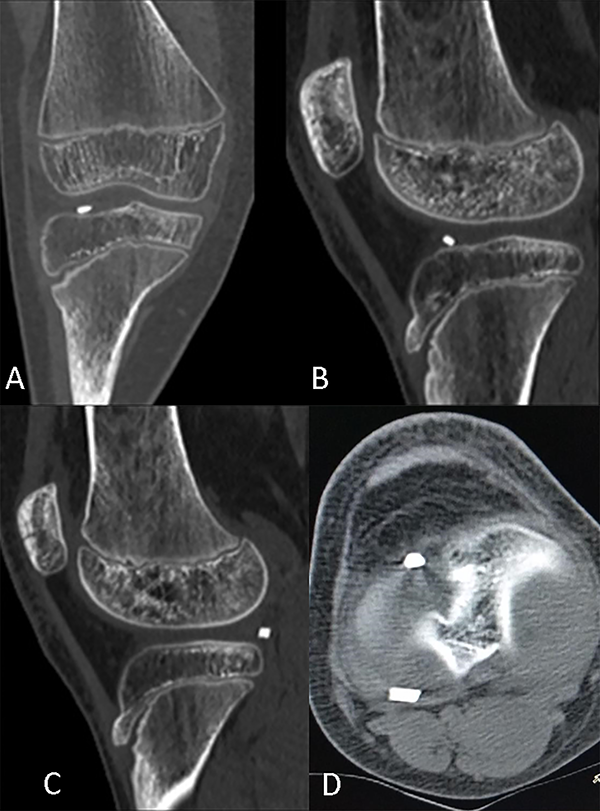

Previo a realizar la tomografía, la paciente reconsultó por aumento del dolor y el derrame articular. Esta vez presentaba déficit a la extensión y maniobra de McMurray positiva. Se realizó el estudio de imagen en el que se visualizaron dos cuerpos intraarticulares compatibles con vidrio, tanto en la región anterior como posterior del compartimento lateral (figs. 3 y 4).

Figura 3. TAC de rodilla derecha. A: Corte coronal. B y C: cortes sagitales. D: corte axial. Se constatan dos fragmentos intraarticulares en el compartimento lateral.

Figura 4. Intensificación de fragmentos en TAC con reconstrucción 3D.

Sobre la base de la evolución clínica, e interpretando los exámenes complementarios, lo que inicialmente en la radiografía se asumió como una lesión de la espina tibial era un fragmento único de vidrio localizado en la región anterior del intercóndilo, y luego en la TAC posterior a la exacerbación de los síntomas mecánicos dicha pieza se encontraba fragmentada y desplazada hacia el compartimento externo.